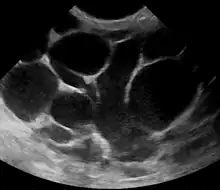

An ultrasound image of puerperal mastitis

Puerperal mastitis is the inflammation of the breast in connection with pregnancy, breastfeeding or weaning. Since one of the most prominent symptoms is tension and engorgement of the breast, it is thought to be caused by blocked milk ducts or milk excess. It is relatively common; estimates range depending on methodology between 5–33%. However, only about 0.4–0.5% of breastfeeding mothers develop an abscess.[11]